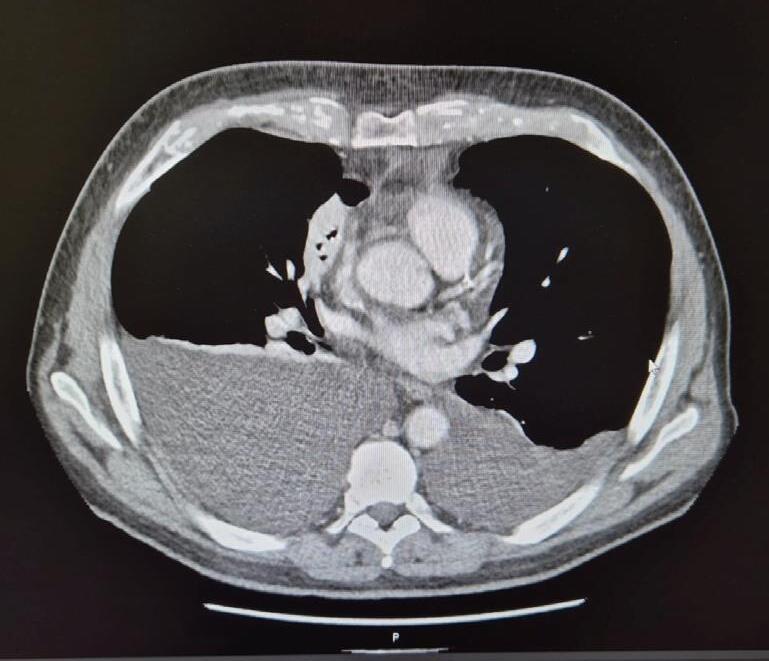

TERAPIE MIRATE PER IL CARCINOMA TIROIDEO AVANZATO: NUOVE FRONTIERE NEL TRATTAMENTO DEL TUMORE RADIO-REFRATTARIO – LINEE GUIDA ESMO

Laura D. Locati, Alfredo Berruti, Cosimo Durante, Sebastiano Filetti